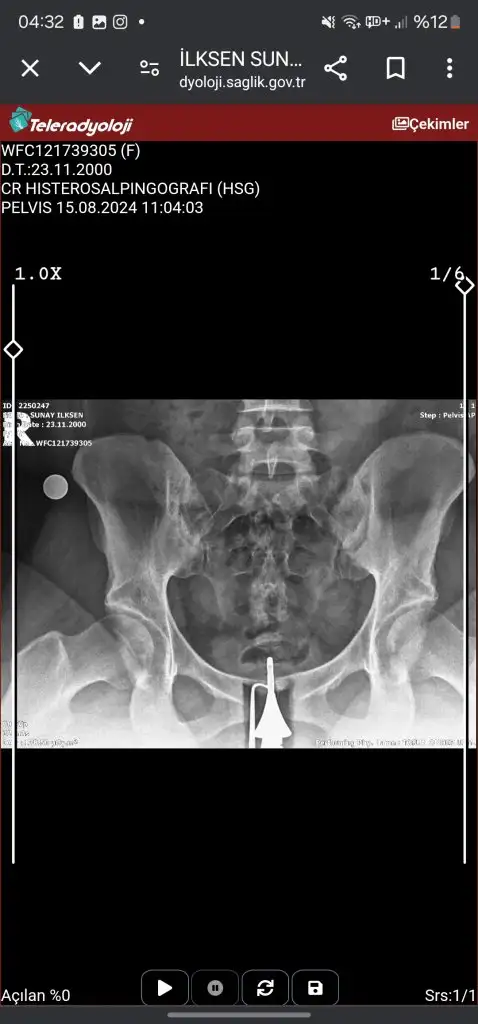

Canım tek tüpün kapalı galibaKızlar acil sonucuma bakarmısınızz ben hiçbirşey anlamıormm